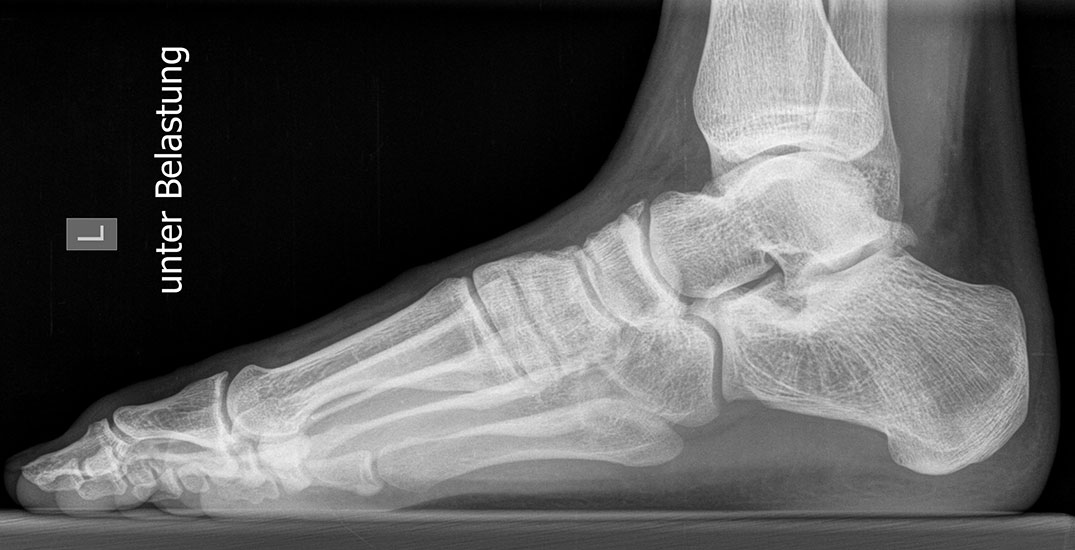

Standard ist die belastete Röntgenaufnahme des Fußes dorso-plantar und seitlich. Günstig ist eine Röhrenkippung von 10°-20°, um die Gelenke der Lisfranc-Linie einsehen zu können.

Ergänzend kann eine Schrägaufnahme hilfreich sein. Bei Metatarsalgien oder Pathologien der Sesambeine liefert die Sprinteraufnahme zusätzliche Informationen. Bei einer Pes planovalgus Fehlstellung wird ergänzend ein Saltzman view durchgeführt.